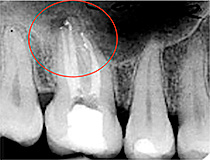

Beispiel für eine Wurzelkanalbehandlung

Oberkiefermolar mit chronischer Entzündung an der Wurzelspitze und Ausheilung nach einem Jahr